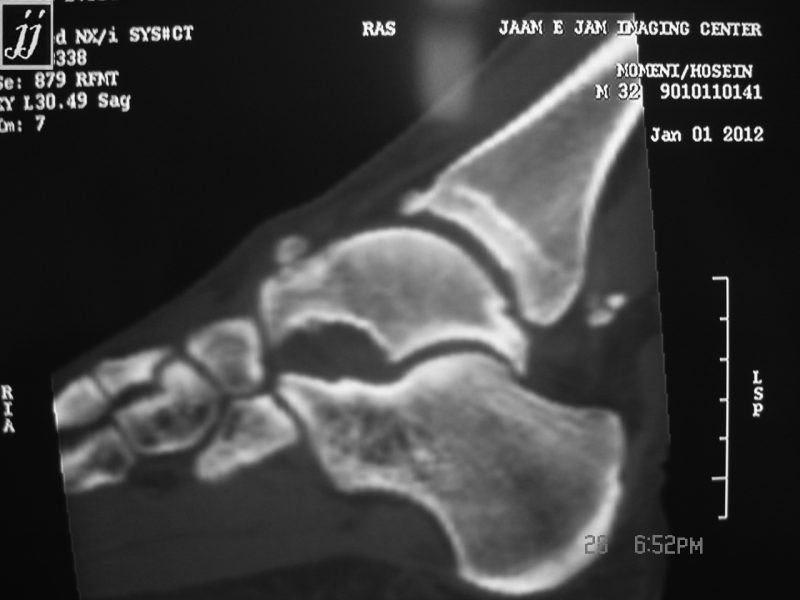

From radioogle.ir

MSK subchondral bone defect of talus and posterior tibia talar loose Talus Bone Spur tibiotalar impingement is a source of anterior ankle pain that is most often caused by osteophyte impingement in the anterior tibiotalar. a bone spur is a growth of extra bone where two or more bones meet that forms as the body tries to repair itself. They also can form on the bones of the spine. bone spurs. Talus Bone Spur.